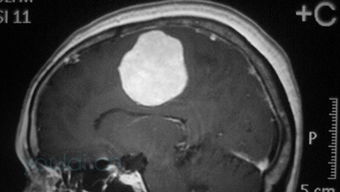

经过一段时间的治疗和休养,我逐渐恢复了健康。然而,在一次例行复查中,医生突然告诉我一个令人震惊的消息:我在之前的CT检查中已经显示出脑瘤的存在,但由于当时情况紧急,医生们没有及时告知我这一信息。这个消息让我感到非常困惑和愤怒。

得知自己患有脑瘤后,我和家人陷入了深深的忧虑之中。我们开始四处打听,寻找最好的治疗方案。经过多方咨询,最终决定接受开颅手术。这是一个非常重大的决定,因为这意味着我要面对巨大的风险。但是为了能够活下去,我没有别的选择。